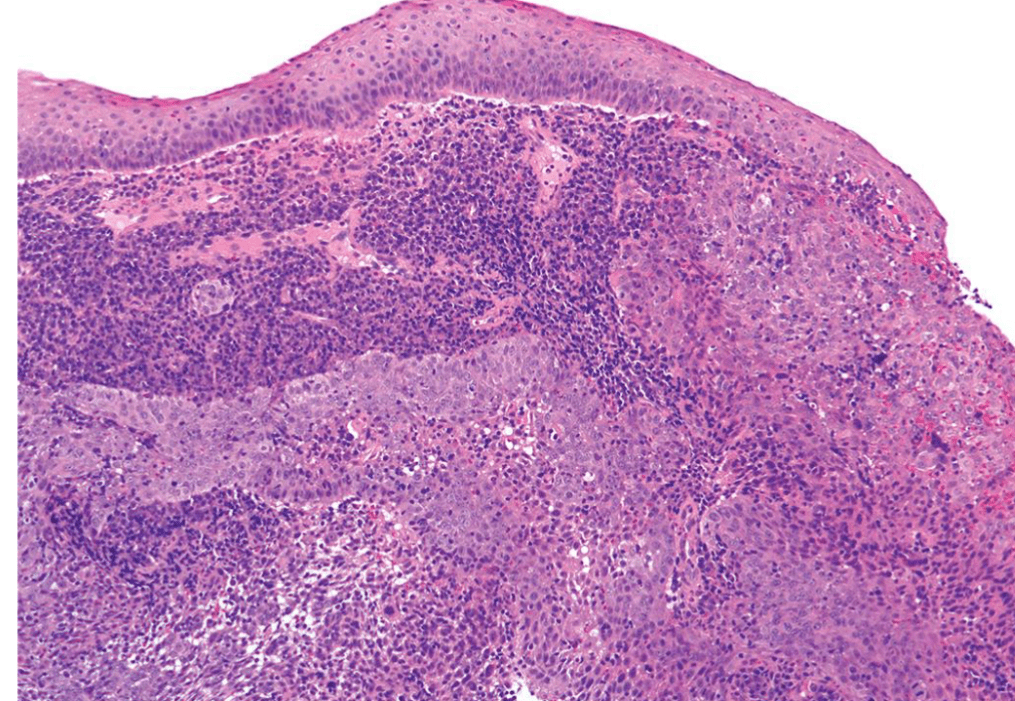

lung adenocarcinoma